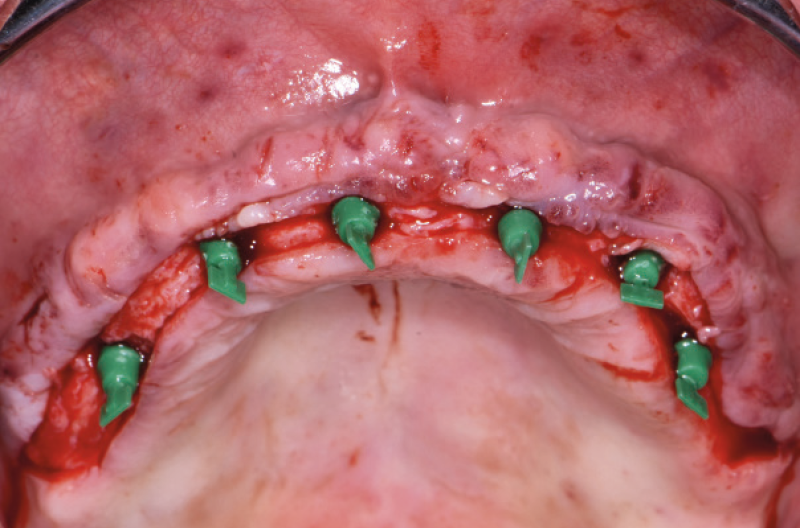

Ho riaperto il mascellare superiore con un lembo a spessore parziale palatino e con scarichi solo distali per limitare al minimo il trauma allŌĆÖosso perimplantare; dopodich├® ho scelto i monconi MUA pi├╣ idonei, tutti GH 1,5 mm uno diritto, tre angolati a 15┬░ e due angolati a 25┬░. Una volta parallelizzati, ho attivato i monconi MUA negli impianti e avvitato gli adattori Conic per trasformarli in monconi MUA-Conic. Dopo aver suturato il lembo, ho attivato le cappette Fixed sui monconi MUA-Conic e poi si ├© proceduto alla ribasatura della protesi opportunamente scaricata in corrispondenza dei monconi MUA-Conic. Durante la procedura intraorale di inglobamento delle cappette Fixed, la protesi si ├© autocentrata in occlusione con la protesi conometrica fissa provvisoria inferiore. Infine la protesi ├© stata rifinita, riposizionata in bocca e attivata (Figg. 30-37). A distanza di un mese entrambe le Toronto provvisorie sono state rimosse e ribasate per un migliore condizionamento del tessuto gengivale (Fig. 38).

Fig. 32 – Posizionamento e parallelizzazione dei monconi MUA

Fig. 33 – Adattatori Conic avvitati sui MUA per trasformazione in monconi MUA-Conic

Fig. 34 – Vista occlusale dei monconi MUA-Conic

Fig. 35 – Cappette Fixed posizionate sui monconi MUA-Conic